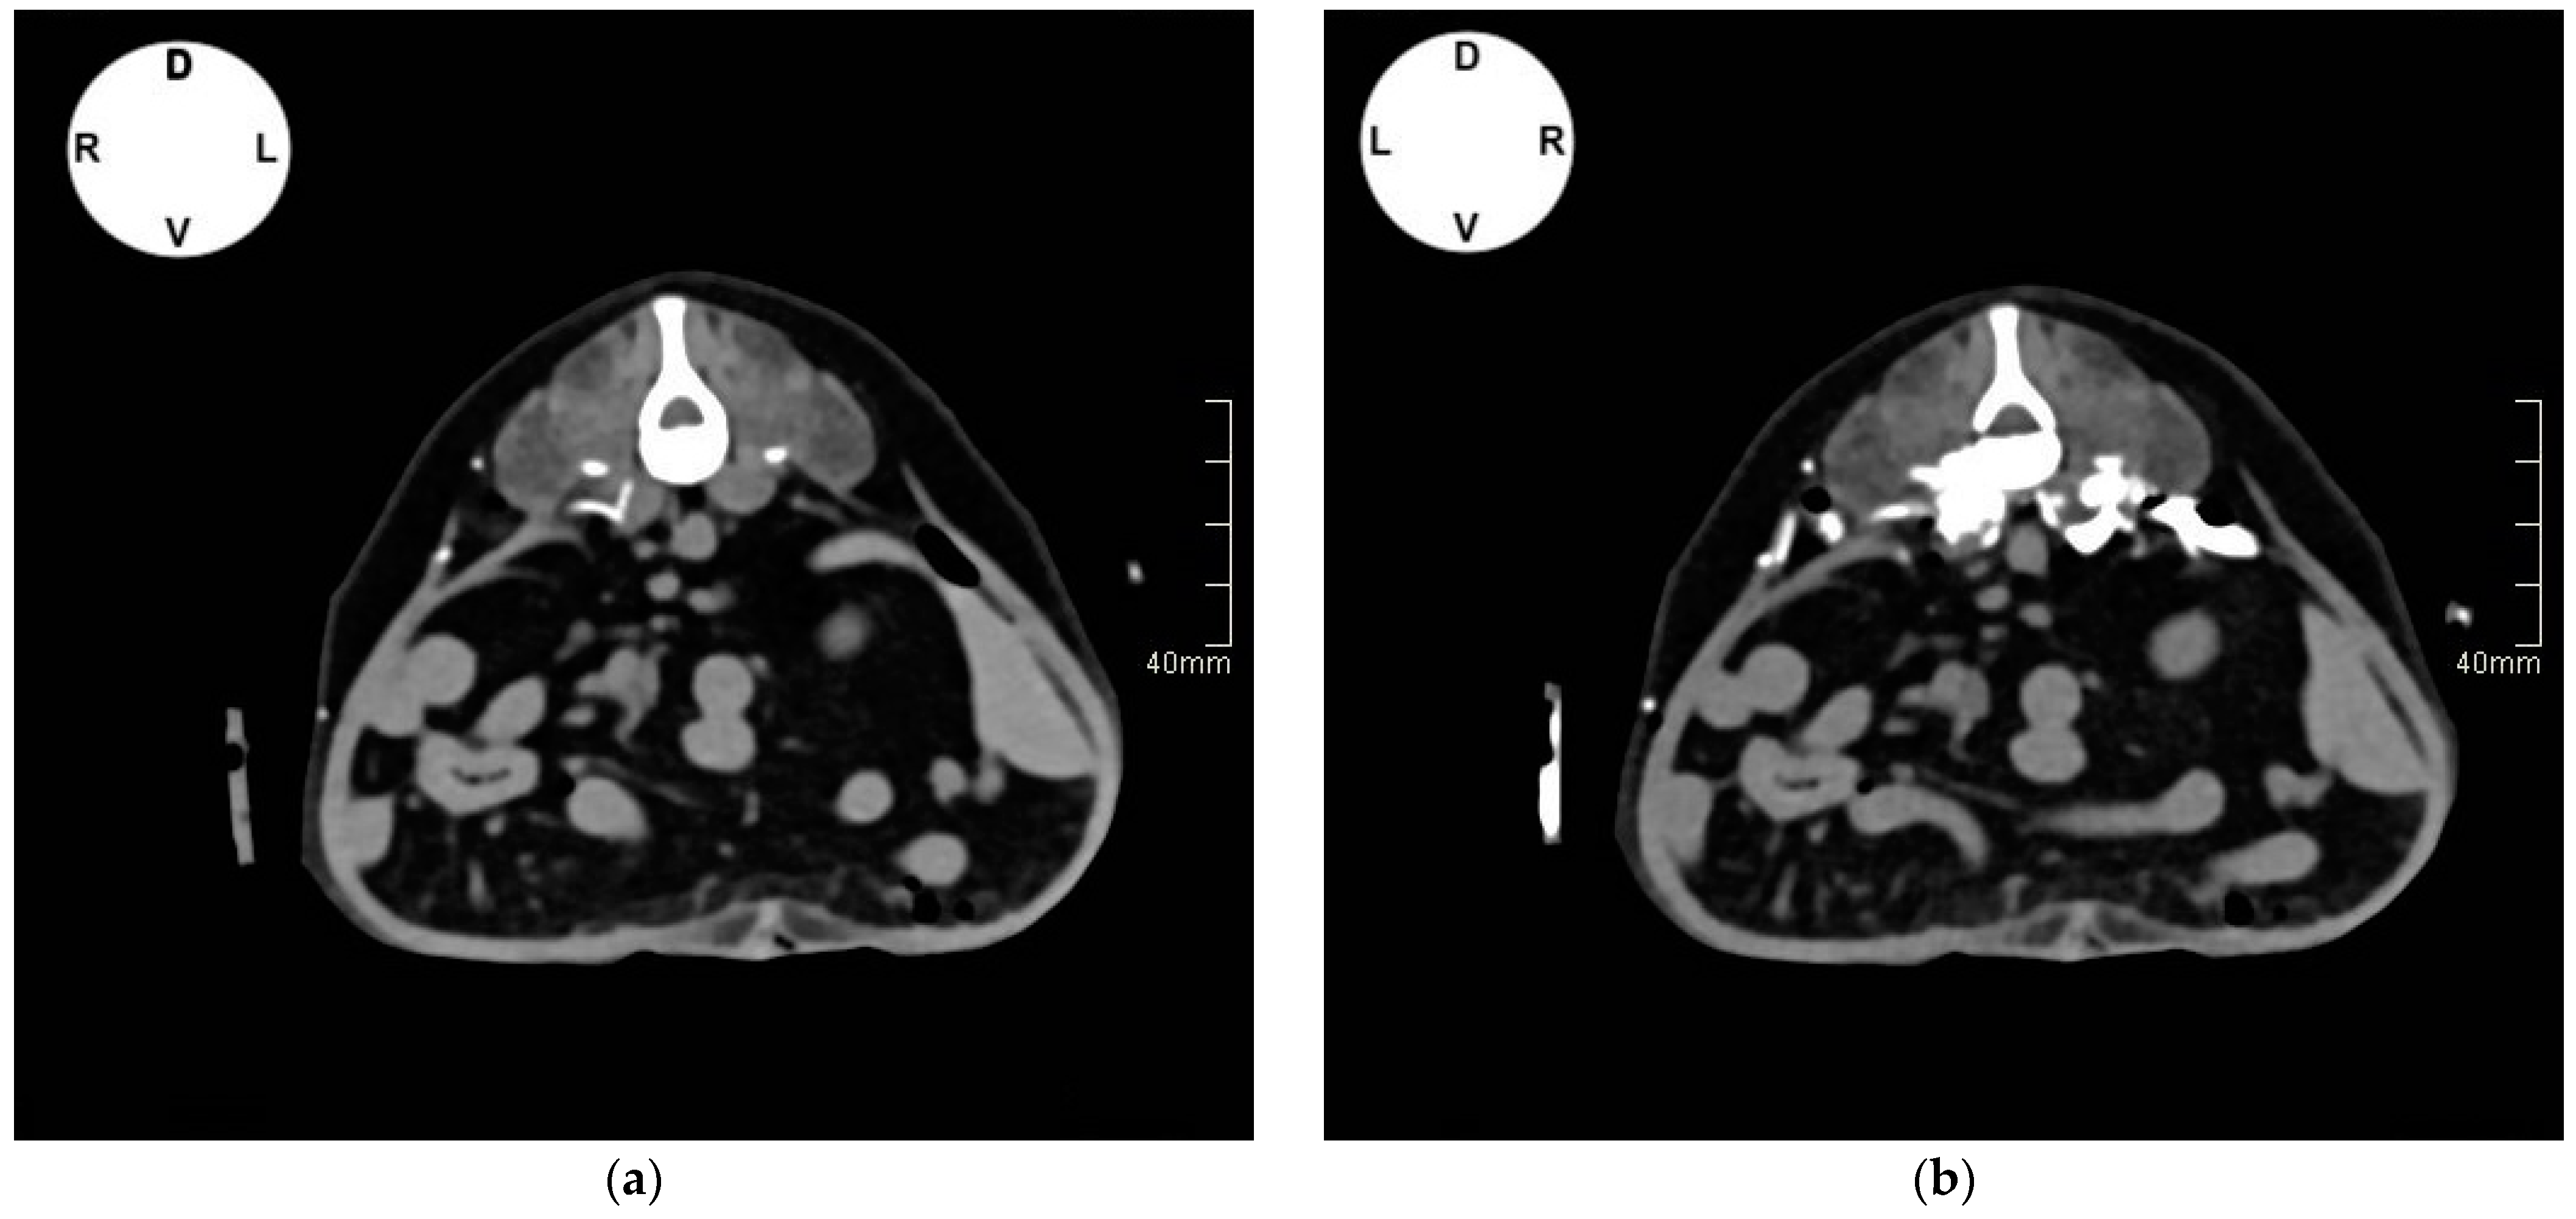

2.1.2. Tomographic Study

3.1.2. Tomographic Study